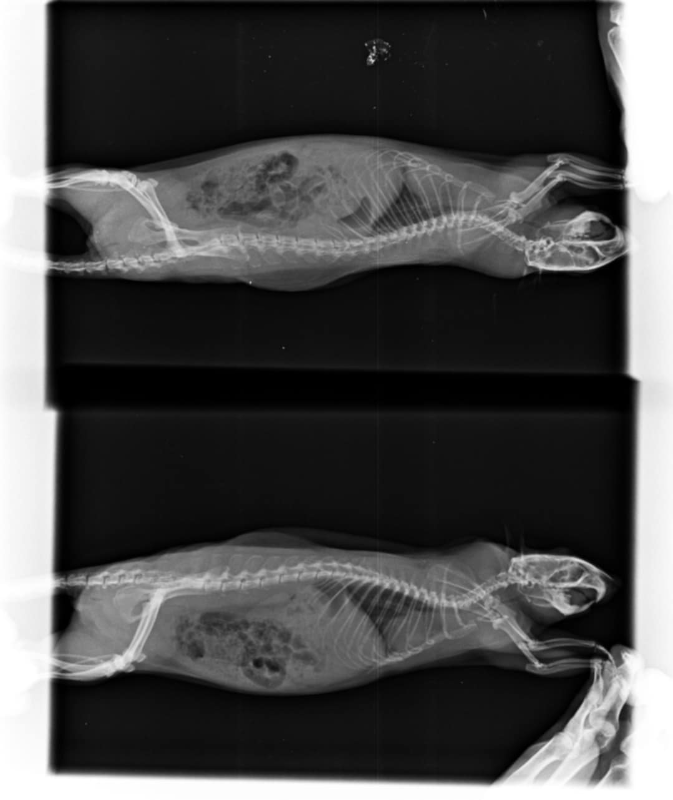

Radio du 12 mai:

Messenger_creation_405C0D98-340E-499F-B66E-C15ED85CE621.png.f4a641b99a04b2beb5ffee18ba1337e6.pngMessenger_creation_7D074FAC-7A52-4F75-B187-71C448B07FB3.png.1e0bb01bf8a2847b489760fa7057450f.png

Les radios sont pas terribles, pas très bien exposées ni assez centrées sur la cage thoracique et floues, du coup perso j'arrive pas à voir grand chose >< Mais bon tes vétos ont sans doute davantage l'habitude. Par contre je trouve aussi que le cœur est gros.